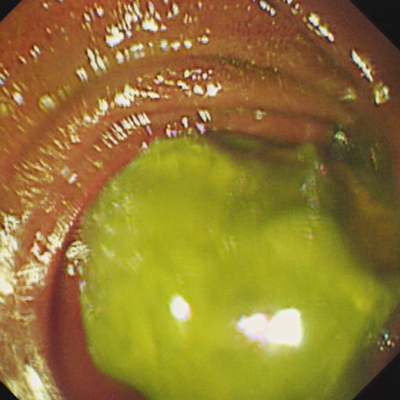

近日,我院消化内科收治了一名“肠梗阻”的婆婆。经检查及多次询问患者,发现患者发病前曾经吃了柿子及山楂等富含大量鞣酸的水果,而原本多发于胃内的胃石,竟然进入了空肠上段。医生介绍,普通的胃镜无法到达空肠上段,无法将“石头”取出,如果无法经内镜取石,婆婆就要到外科通过开腹手术“取石”。经科室专家反复讨论,决定在没有小肠镜的情况下,运用结肠镜进入空肠“取石”。

最终,内镜护士配合经验丰富的内镜专家,经过一个多小时的努力,几经周折终于将结肠镜送达空肠,找到并顺利将“石头”取出。术后婆婆腹痛、腹胀好转,排便排气正常,可以正常进食。出院时婆婆向医护人员竖起了大拇指,表达了她的感激之情。